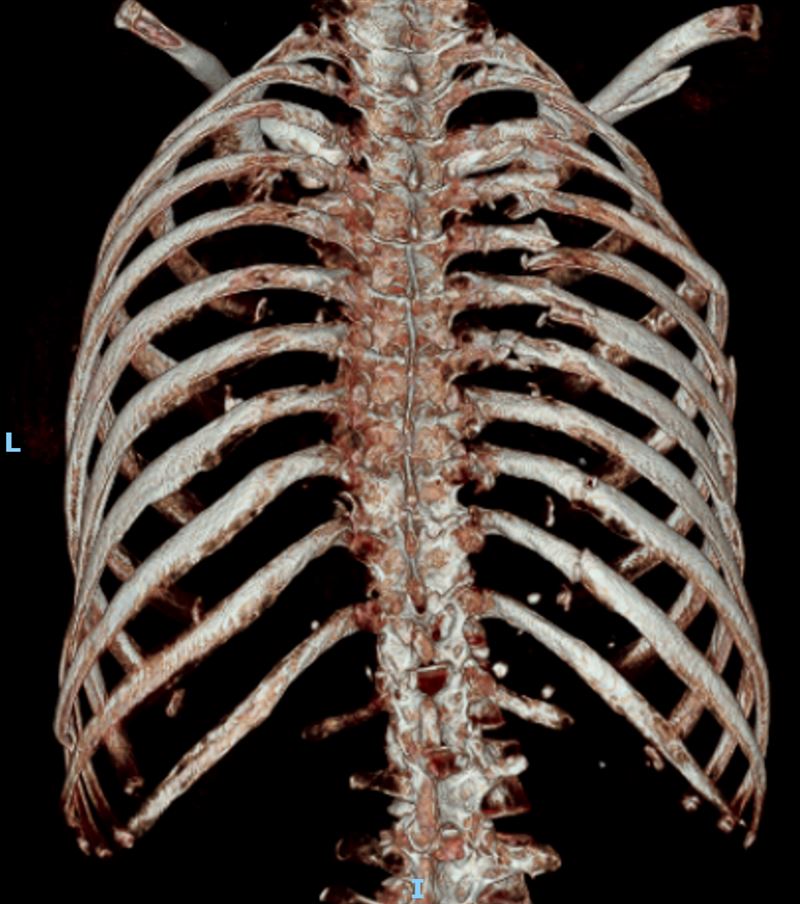

一名70歲黃婦車禍重傷,肋骨斷21處、歷經7次手術,仍堅強求生,「我想活下去」的意志感動醫護,奇蹟重生。(圖/衛福部彰化醫院提供)

一名70歲黃姓婦人9月初車禍重傷,隨即被送往衛福部彰化醫院,全身骨頭斷得支離破碎,光是肋骨就斷了21處,破碎的骨頭如同散落的拼圖,血壓驟降,歷經3科醫師共7次手術。過程中黃婦始終堅強面對,展現出「我想活下去」的力量,讓醫護們動容,為她拚命,從鬼門關裡被搶救出來。

林聿騰指出,整個變形的胸腔透過3D胸廓重組影像定位後進行微創手術,以鈦合金骨板及骨釘進行肋骨固定,穩定整個胸腔,讓患者可以正常呼吸,再交由骨科手術。